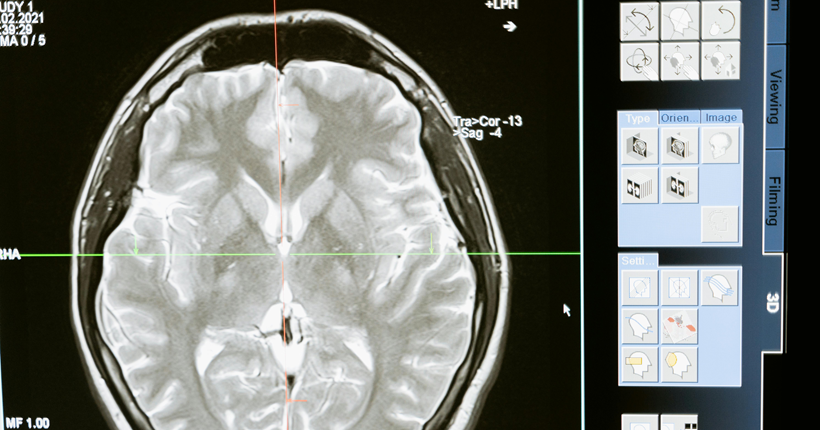

Julio Antonio Esquivel-Tamayo1, Arquímedes Montoya-Pedrón2 | 1 Doctor en Medicina. Residente de Tercer Año en Medicina Familiar. Doctorando en Ciencias Médicas. Diplomado en Medicina Natural, Tradicional y Apiterapia. Profesor Instructor. Universidad de Ciencias Médicas de Las Tunas. Policlínico Docente Manuel Fajardo Rivero. Las Tunas, Cuba. 2 Doctor en Ciencias Médicas. Especialista de Primer y Segundo Grado en Neurofisiología Clínica. Profesor e Investigador Titular. Jefe del Servicio de Neurofisología del Hospital General Dr. Juan Bruno Zayas Alfonso. Universidad de Ciencias Médicas de Santiago de Cuba. Santiago de Cuba, Cuba. La enfermedad de Alzheimer, constituye un problema sanitario y social de gran magnitud; precisa de diagnóstico y terapéutica precoces. Dispersos estudios de diversa metodología se refieren a la predicción de la demencia a partir de factores de riesgo. No obstante, existen insuficientes investigaciones que analicen en conjunto factores de riesgo y biomarcadores y los asocien; lo que ha limitado la posibilidad de acciones preventivas y terapéuticas precoces en pacientes en riesgo. Se realizó una revisión sistemática de la literatura con el objetivo de analizar los factores de riesgo y los biomarcadores de la enfermedad de Alzheimer. Se realizó una búsqueda de los términos: "demencia/ dementia", "enfermedad de Alzheimer/ Alzheimer’s disease" "factor de riesgo/ risk factor", "biomarcador/ biomarker", en las bases de datos: PubMed/Medline, Scopus, Scielo, Lilacs y mediante el buscador Google académico; se consultaron documentos no publicados. Se clasificaron los resultados de la búsqueda mediante el examen del título y resumen. De 154 investigaciones encontradas se incluyeron revisiones, metaanálisis, estudios observacionales y ensayos publicados desde el año 2017 hasta el 2023, en idioma español, inglés y portugués. Se excluyeron trabajos duplicados, libros o capítulos de libros, estudios cualitativos, que no se relacionaran con el tema o sin acceso al texto completo. Tras la aplicación de los criterios, se obtuvieron 32 estudios observacionales, 23 revisiones, 12 metaanálisis, y 3 ensayos. Se revisaron los documentos completos para verificar el cumplimiento de los criterios de inclusión. Los principales factores de riesgo encontrados son edad avanzada, menor educación, poca actividad física, hábito de fumar, consumo excesivo de alcohol, hipertensión arterial, diabetes, obesidad, depresión, pérdida o disminución de la audición, aislamiento social, los traumas craneales y la contaminación ambiental. Los biomarcadores fundamentales son: los marcadores que se utilizan en los estudios de neuroimágenes como la tomografía por emisión de positrones (PET) Amiloide, PET tau, PET con fluorodesoxiglucosa (FDG); y en líquido cefaloraquídeo y plasma: Aβ42, Aβ42/Aβ40, p tau 217, p tau 181, proteína gliofibrilar ácida (GFAP), y neurofilamentos de cadena ligeras. Se reconoció el uso de los parámetros cuantificados en el P300 como biomarcadores complementarios clasificadores de la presencia y del nivel de disfunción cognitiva de etiología enfermedad de Alzheimer posible. La mayoría de los estudios analizados, aunque abordan con profundidad la relación de los factores de riesgo y la enfermedad de Alzheimer, tienen limitaciones al asociar unos factores con otros, o con biomarcadores. Se requieren estudios longitudinales, a partir de la presencia de los factores de riesgo asociados a biomarcador, desde edades pregeriátricas en pacientes sanos, que tengan como salidas el deterioro cognitivo y el desarrollo de la demencia, para construir un modelo de predicción. Leer el artículo completo

Juan de Jesús Llibre-Rodríguez 1, Raul Fernando Gutiérrez Herrera 2 | 1 Unidad del Declinar Cognitivo y las Demencias, Universidad de Ciencias Médicas de La Habana (Cuba), 2 Departamento de Medicina Familiar, Universidad Autónoma de Nuevo León. Monterrey. México En el mundo 56 millones de personas viven con demencia. Se estima que este número se incrementará a 82 millones en 2030 y 152 millones en 2050, representando uno de los retos más serios que enfrentará la salud pública en los próximos años. El diagnóstico temprano de las demencias es de extrema importancia, al permitir la evaluación de causas reversibles, mejorar la atención de enfermedades comórbidas, guiar la selección de tratamientos sintomáticos y modificadores de la enfermedad adecuados, identificar las necesidades de apoyo social, la planificación de la familia y de la propia persona que vive con demencia en aspectos familiares, medicolegales y de su vida futura. Sin embargo, el diagnóstico temprano y preciso de la EA en la práctica clínica es un gran desafío. Actualmente el diagnóstico clínico de la EA es limitado; alrededor del 20 %-30 % de los pacientes no se diagnostican adecuadamente, si no se utilizan biomarcadores en líquido cefalorraquídeo (LCR), sangre o mediante tomografía de emisión de positrones u otros estudios de neuroimagenes. La aprobación reciente de tratamientos modificadores de la enfermedad y el rápido desarrollo durante la última década de biomarcadores, que permiten un diagnóstico preciso de la enfermedad de Alzheimer incluso antes de la aparición de los síntomas clínicos, nos acerca cada vez más a la curación o detención de la progresión de la enfermedad. Esta imagen en rápida evolución ha ido acompañada de un mayor desarrollo en nuestra comprensión de cómo se puede prevenir la demencia actuando sobre sus factores de riesgos, modificaciones en los estilos de vida e intervenciones en el curso de la vida. En el futuro se podrán utilizar biomarcadores en la atención primaria de salud para identificar a los pacientes con deterioro cognitivo que necesitan ser referidos para una evaluación cognitiva adicional por especialistas en trastornos de la memoria, como mismo se utilizan otros marcadores, por ejemplo, el Antígeno prostático especifico (PSA) en el diagnóstico del cáncer de próstata. La relación Aß42/Aß40, la determinación de la proteina p-tau, y neurofilamentos NfL, pueden representar excelentes candidatos para implementarse en atención primaria. En atención primaria los biomarcadores digitales (pantallas digitales, teléfonos móviles y otros) se podrán utilizar para preseleccionar individuos en riesgo de deterioro cognitivo que podría beneficiarse de estudios con biomarcadores en sangre. En personas de 55 años y más que refieran quejas subjetivas de memoria u otro síntoma sugestivo de un síndrome cognitivo conductual corroborado por un informante confiable, o aquellos con antecedentes familiares de demencia y factores de riesgo conocidos, se profundizará en su historia clínica incluida medicación concomitante, conjuntamente con una evaluación cognitiva y conductual, examen físico/neurológico y la indicación con juicio clínico de los biomarcadores e imágenes estructural del cerebro. El desarrollo futuro de los biomarcadores, permitirá el diagnóstico de la enfermedad de Alzheimer desde los estadios asintomáticos y un mayor beneficio en el tratamiento de los pacientes. Ello requiere una mayor prioridad por los gobiernos ante el creciente reto que representan las demencias. Leer el artículo completo

BALEA-FERNÁNDEZ, FRANCISCO JAVIER [1]; ALONSO-RAMÍREZ, JAVIER [2]. | [1] DOCTOR EN PSICOLOGÍA (USAL) Y DOCTORANDO EN INVESTIGACIÓN EN BIOMEDICINA (ULPGC); [2] DOCTORANDO EN INVESTIGACIÓN EN BIOMEDICINA (ULPGC). El envejecimiento de la población en España es una cuestión que no solamente atañe a la salud de la población y a Sanidad, sino que tiene importantes repercusiones en la economía, estructura familiar, sostenibilidad del sistema de pensiones, etc. Supone un elevado gasto sanitario, como ejemplo: el 52% del gasto de Atención Especializada se dedica a mayores de 65 años y los mayores de 70 años son los responsables del 40% del total del gasto sanitario. Los datos anteriormente expuestos denotan que el sistema sanitario no ha sabido adaptarse a la nueva situación social, aumentando el edadismo (senectismo) y responsabilidad de la sostenibilidad del sistema a la población mayor. La principal herramienta para poder implantar el renovado sistema es la educación sanitaria. La segunda es que las decisiones clínicas sean compartidas entre el paciente, sus familiares, los cuidadores y los proveedores de asistencia sanitaria. El proceso de diagnóstico de Enfermedad de Alzheimer (EA) comienza cuando el paciente, solo o bien con algún familiar, acude a la consulta de atención primaria con quejas de memoria y/o alteraciones en el comportamiento (en este caso, acompañado/a siempre por familiares). En esta primera consulta, lo más frecuente es que la demencia se encuentre en fase leve/moderada. La principal característica de la EA en la actualidad es que se trata de una enfermedad neurodegenerativa de etiología aún no está establecida. En la búsqueda etiológica se han estudiado casos determinados genéticamente: autosómico dominante supone menos del 1 % de todos los casos; el 99% de los casos de EA se produce por otros mecanismos ajenos a la genética. Los biomarcadores de depósito amiloide y de neurodegeneración (obtenidos del líquido cefalorraquídeo: péptido Aß1-42 y las proteínas Tau total y Tau fosforilada, o bien por técnicas de neuroimagen (resonancia magnética (RM) o tomografía por emisión de positrones (PET con18F-fluorodesoxiglucosa PET-FDG) (procedimiento ATN). Los biomarcadores en sangre periférica aún no están estandarizados para el diagnóstico clínico. En la actualidad se están realizando trabajos para la determinación de biomarcadores en sangre periférica utilizando imagen hiperespectral. Esta técnica tiene como objetivo la búsqueda de diferencias entre plasma de pacientes con/sin EA. Este trabajo está en la actualidad en fase de experimentación. En relación con el tratamiento específico de la DTA, se divide en tratamiento farmacológico y no farmacológico, así como tratamiento para los síntomas cognitivos y no cognitivos. Los biomarcadores proporcionan un nuevo horizonte sobre el diagnóstico en fase preclínica y aportan datos sobre la etiología de la EA. Estos horizontes proporcionan nuevas líneas de investigación tanto para el diagnóstico etiológico como para la aportación de tratamientos efectivos en la DTA. Pulse para leer el artículo completo